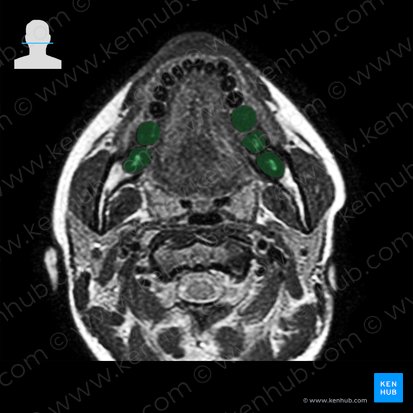

Dente molar

Estrutura e relações anatômicas do dente.

Na dentição adulta, os molares são os dentes amplos e planos localizados posteriormente aos pré-molares. Os molares são os dentes mais especializados em triturar ou moer os alimentos, devido às suas coroas largas e pontas arredondadas. Na maioria dos adultos, existem um total de doze molares: seis superiores e seis inferiores (três de cada lado em cima e três de cada lado em baixo). Os molares mais posteriores, os terceiros molares, também são chamados de dentes sisos. Eles são os últimos a sofrer erupção, e são comumente removidos por conta de complicações.

A estrutura geral dos molares é semelhante à dos outros dentes. Eles possuem três regiões: a coroa (revestida por esmalte), o colo (cercado pela gengiva) e a raiz (interna ao osso). Diferentemente dos outros dentes, os molares superiores possuem três raízes cada, enquanto os molares inferiores possuem duas raízes cada.